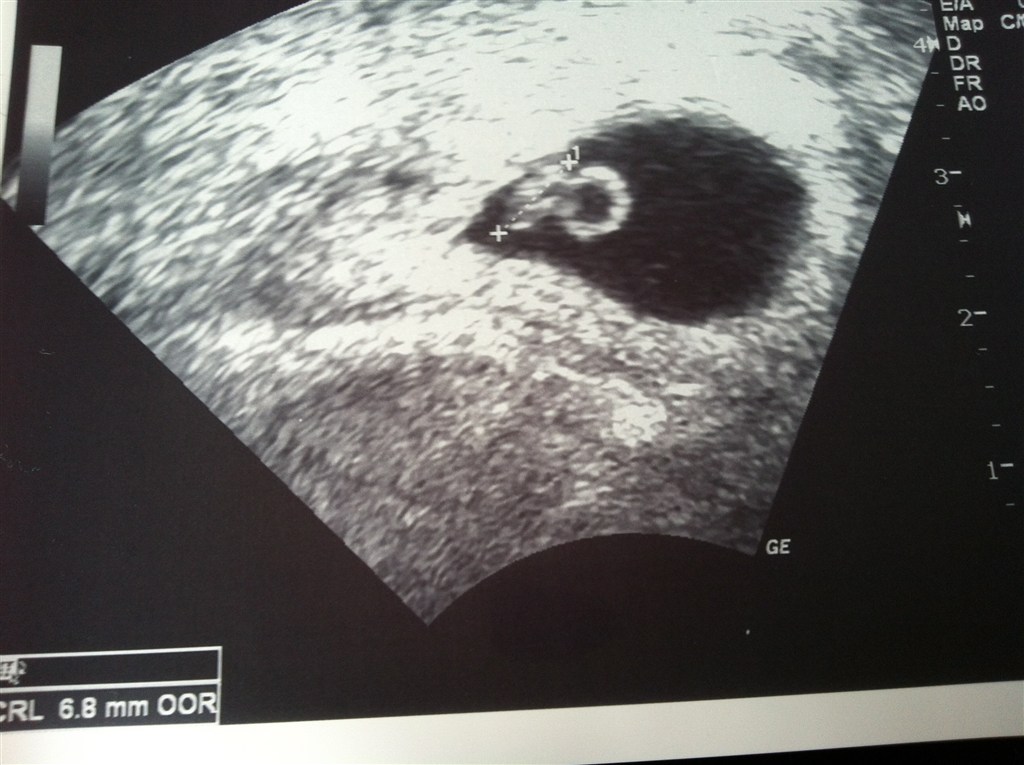

Viste en dejlig lille reje med et smukt blinkende hjerte!

Den lille bebsi har allerede nu efterabet sin storebror, da vi så ham ved samme "alder" til scanning for 2 år siden, og medbragt en flot stor blommesæk (boblen til højre for rejen).

Terminen blev rykket til den 29 December, så er idag 6+6

Ih hvor var det bare fantastisk at se dens lille hjerte galopere derud af